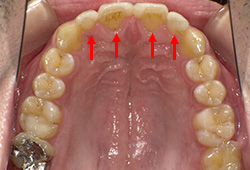

右上654をジルコニアフレームセラミックブリッジにて修復(赤矢印)

左上456をセラミックインレーにて修復(青矢印)